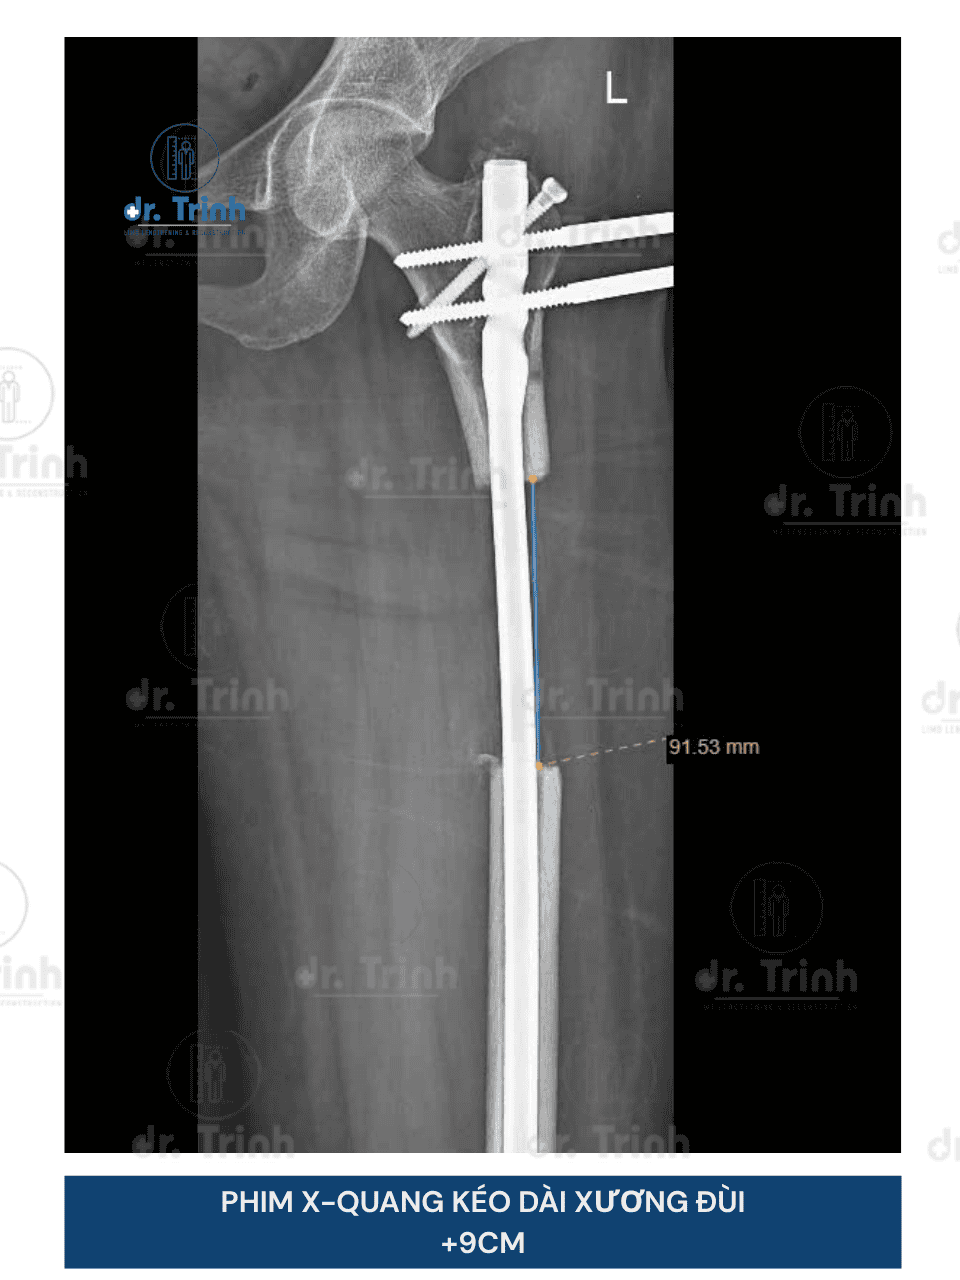

Phẫu thuật kéo dài chân là phương pháp phẫu thuật giúp cải thiện chiều cao giúp cho những người muốn cải thiện chiều cao và vóc dáng. Trong nhiều trường hợp, phẫu thuật kéo dài chân còn giúp điều chỉnh các bất cân xứng chi (chân lệch, chân ngắn bẩm sinh, chênh lệch chiều dài chân sau chấn thương), có thể góp phần mang lại sự cân đối và chức năng vận động tốt hơn.

- Phương pháp phẫu thuật: Đinh nội tủy tự động Precice, khung tròn, khung thẳng mới..

- Vị trí kéo dài: Kéo dài xương đùi hoặc xương cẳng chân có chi phí khác nhau